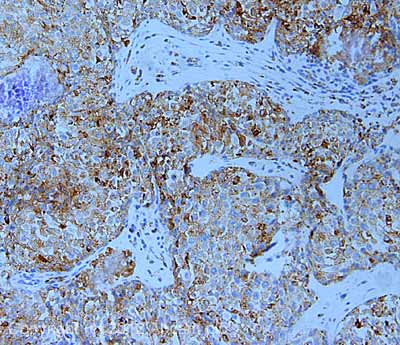

Anti-LAMP2A antibody - Lysosome Marker(AB18528)

Anti-LAMP2A antibody ab18528 is a rabbit polyclonal antibody that is used in LAMP2A western blotting, IHC and immunofluorescence. Suitable for human and mouse samples.

Applications ICC/IF, IHC-P, WB

Species Reactivity Human, Mouse